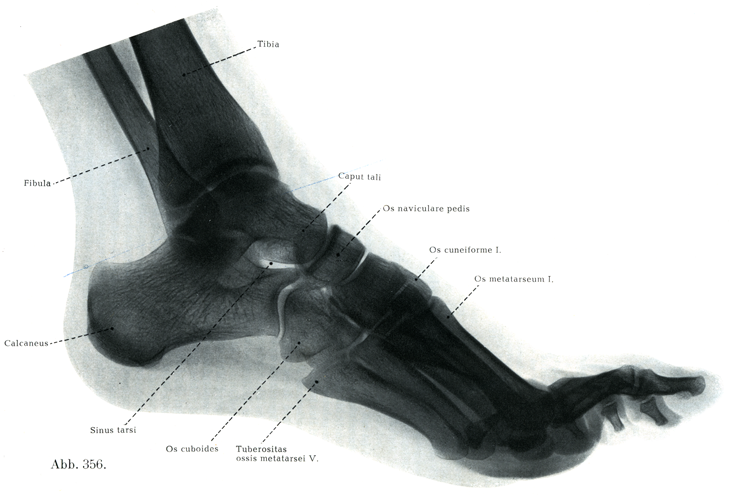

[図353]足の骨(右)足背面(6/7)

H. Virchow作製の標本(凍結骨格処理法によって,骨の相互の自然の間隔と正しい向きを保って組立てられている)

[図356]足の骨格のレントゲン像 21才の少女,内側から外側へ照射(2/3)